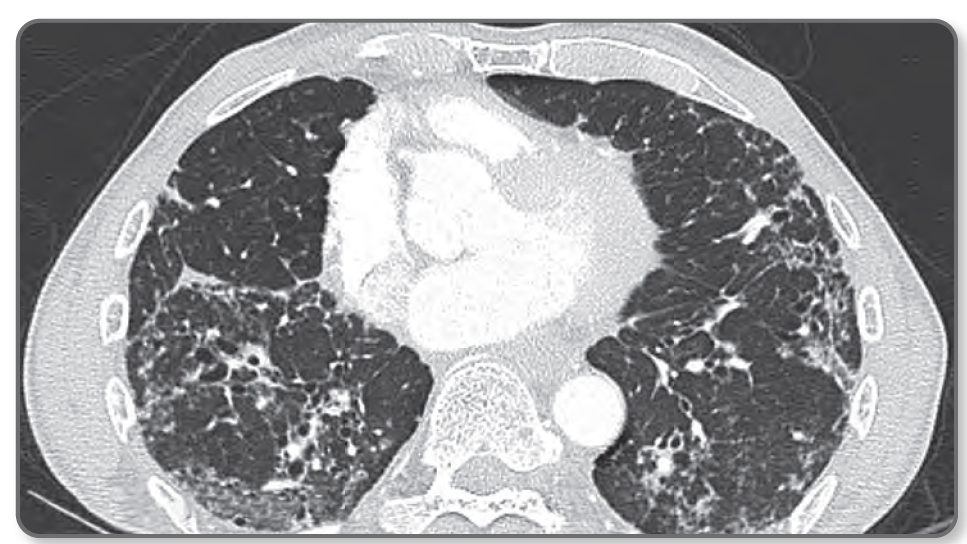

1. HRCT Thorax (gold standard)

- Signet ring sign

- Dilatation of airway lumen > 1.5x nearby vessels

- Affecting lower lobes (if upper lobe - suspect CF or ABPA)

- Bronchi ends abnormalities

> Cylindrical/tubular: lack of tapering of bronchi

>Varicose: dilated bronchi with irregular bulging contours/bullae

> Saccular of cystic pus-filled cavities